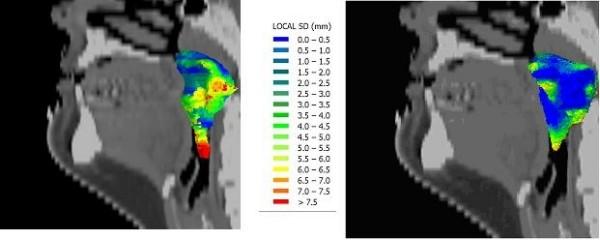

For ten nasopharyngeal cancer patients, ten observers each delineated the Clinical Target Volume (CTV) and the CTV elective. After 3D analysis of the delineated volumes, a second delineation was performed. This implied improved delineation instructions, a combined delineation on CT and co-registered MRI, forced use of sagittal reconstructions, and an on-line anatomical atlas.

Both for the CTV and the CTV elective delineations, the 3D SD decreased from Phase 1 to Phase 2, from 4.4 to 3.3 mm for the CTV and from 5.9 to 4.9 mm for the elective. There was an increase agreement, where the observers intended to delineate the same structure, from 36 to 64 surface % (p = 0.003) for the CTV and from 17 to 59% (p = 0.004) for the elective. The largest variations were at the caudal border of the delineations but these were smaller when an observer utilized the sagittal window. Hence, the use of sagittal side windows was enforced in the second phase and resulted in a decreased standard deviation for this area from 7.7 to 3.3 mm (p = 0.001) for the CTV and 7.9 to 5.6 mm (p = 0.03) for the CTV elective.

材料与方法

结果

无论是 CTV 还是 CTV 选择性勾画,3D 标准差都从第 1 阶段到第 2 阶段降低,CTV 从 4.4 降至 3.3mm,CTV 选择性从 5.9 降至 4.9mm。观察者对同一结构的勾画意向一致性增加,CTV 从 36%增加到 64%(p=0.003),CTV 选择性从 17%增加到 59%(p=0.004)。勾画的最下部边界变化最大,但当观察者使用矢状位窗时,这些变化较小。因此,在第 2 阶段强制使用矢状位侧窗,使 CTV 和 CTV 选择性的该区域标准差从 7.7 降至 3.3mm(p=0.001)和 7.9 降至 5.6mm(p=0.03)。